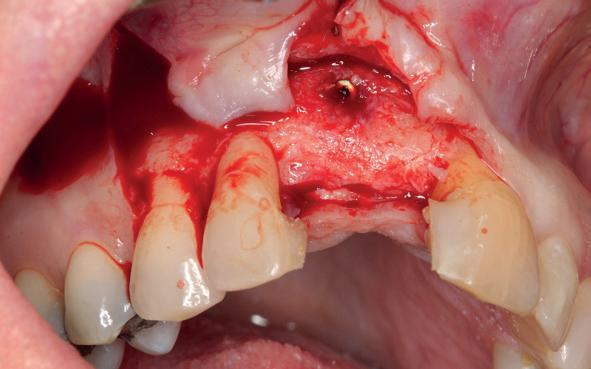

Er werd meer bekend over de gedragingen van het bot rond de “microgap” en daarmee kwam er meer begrip over hoe een implantaat goed te plaatsen in de esthetische zone. In het midden van de jaren negentig kwam daar de kennis bij hoe, op een verantwoorde manier en met behulp van guided-bone-regeneration, een implantaat in de esthetische zone te plaatsen (afbeelding 6-10).

Van vooral functionaliteit verschoof de indicatie naar esthetiek. De zachteweefselchirurgie en vaak voorbehandeling van zachte weefsels voor implantologie kreeg veel meer aandacht (afbeelding 11-14).